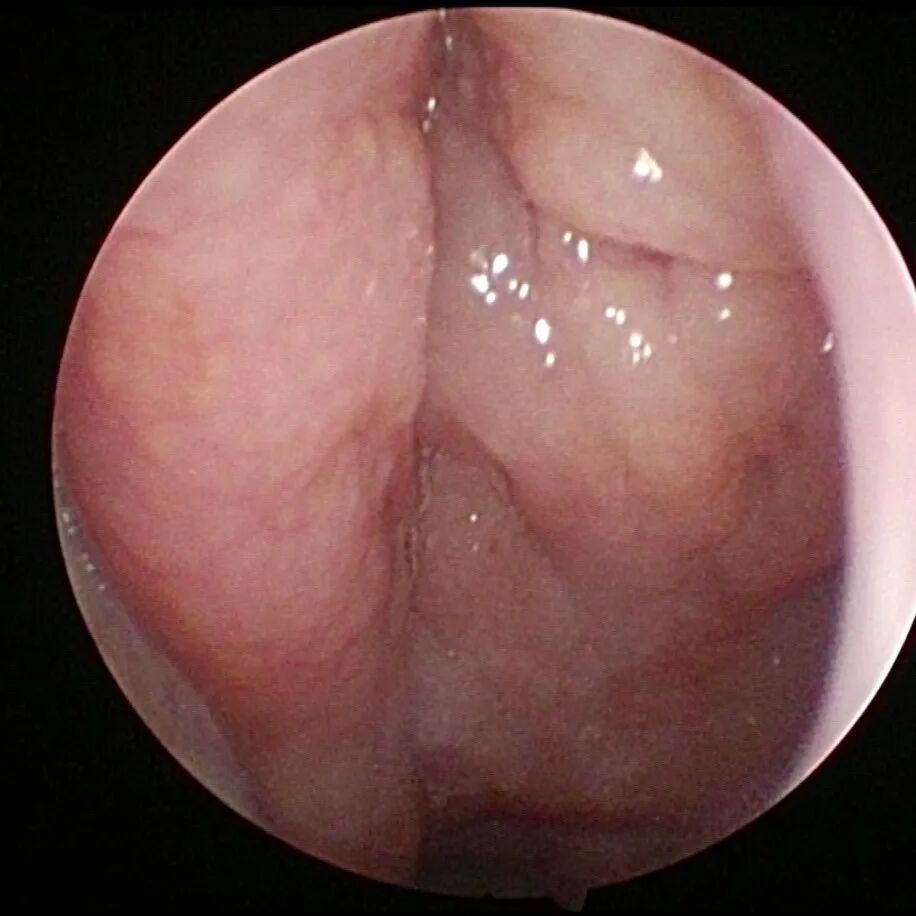

成人腺样体残体

3